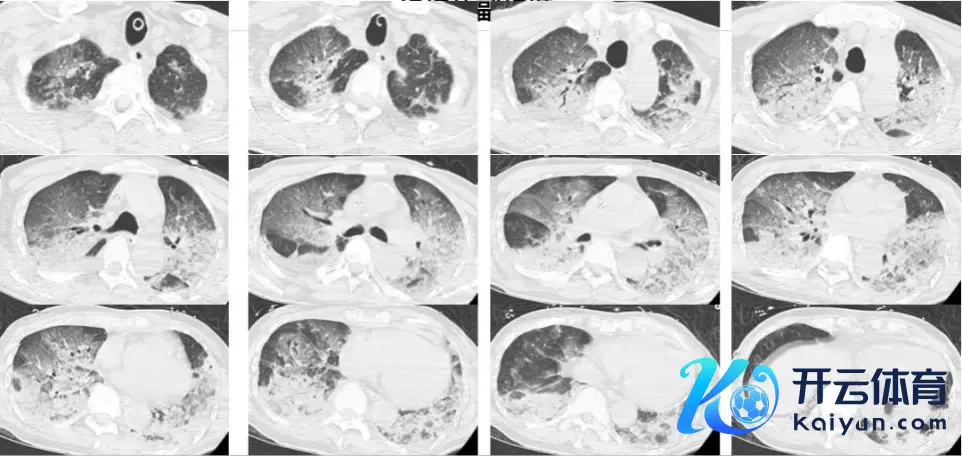

韩大爷插管后被立即送到CT室,进行了头颅、胸部CT和肺血管CTA查验。截止一出来,尽然两肺全白了!

经查验,大夫排除了脑中风和肺栓塞的可能性。流程实时抢救,韩大爷各项查验缱绻有了显然改善,但究竟为何会有这样严重的白肺出现?

病院供图